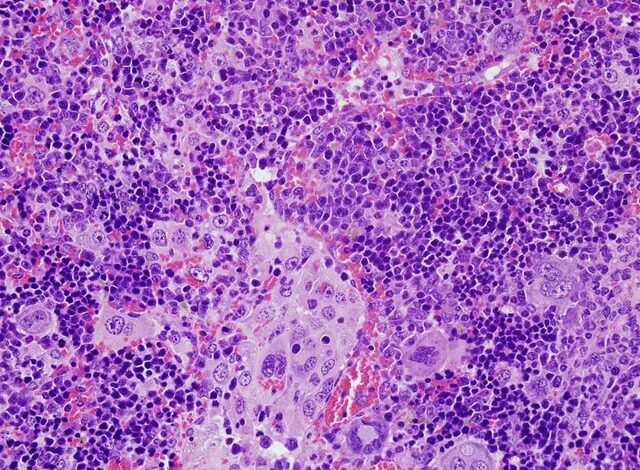

Concretamente, este grupo ha publicado un artículo científico en donde destaca la realización de un catálogo completo de las mutaciones del gen VAV1 que se habían encontrado en distintos tipos de tumores humanos y, con frecuencia más alta, en un tumor originado en células de la sangre que se conoce como linfoma periférico de células T.

En este estudio, cuyo primer firmante es el investigador del CIC y del CIBER de cáncer Javier Robles-Valero, también han demostrado que «el tipo de mutación más frecuente de VAV1 en tumores causa de forma autónoma la rápida aparición de linfomas periféricos de células T cuando se expresa en ratones».

«Junto con la demostración de que estas mutaciones de VAV1 actúan como agentes causales del cáncer, el modelo animal desarrollado en este estudio nos ha permitido desarrollar linfomas de células T que son muy similares a las que se encuentran en pacientes»; ha destacado el doctor Bustelo.